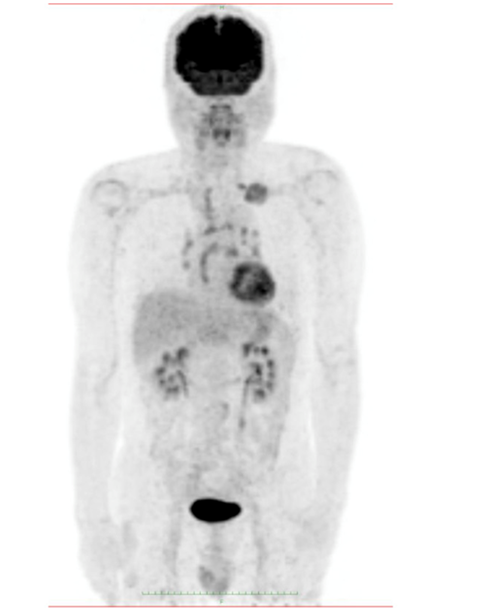

Figure 6 Fluorodeoxyglucose-positron emission tomography shows abnormal uptake in the left lung tumor, bilateral hilar lymph nodes, and left supraclavicular lymph nodes.

The patient consulted with a cardiology team where an electrocardiogram and an exercise test were performed, being reported normal. He was then referred to the orthopedics service due to shoulder pain persistence. A shoulder x-ray showed a tumor in the left thorax measuring 78.99mm in diameter (Figure 1). In follow up studies, a left humeral lesion of neoplastic appearance was revealed. In the magnetic resonance an intramedullary lesion is reported in the sternum, incidentally, a solid mass is observed in the left lung, it also shows tendinitis of the rotator cuff and subacromial impingement (Figures 2-4). Therefore, it is decided to perform a Computed Tomography scan which reported atelectasis mainly in the left upper lobe and a tumor measuring 65mm (Figure 5). The Positron Emission Tomography - Computed Tomography scan result was an increase of the metabolism by neoplastic activity, lymphadenopathy and bone lesions, hepatosplenomegaly and non- specific alterations in the colon (Figure 6).